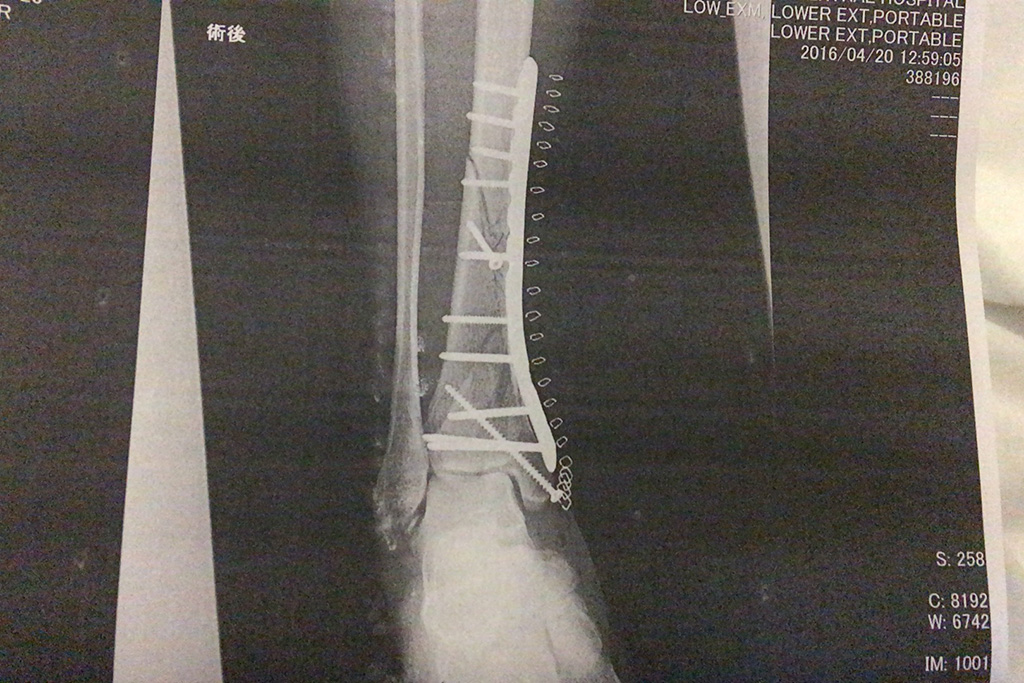

そういえば担当の看護士さんに術後のレントゲンって見れないんだろか?って聞いてみたら、あとでプリントアウトして持って来てあげる♪

ってことで、どーん!

ガッツリプレートが入っていて、ボルトが12本、ホッチキス大量ですねf^_^;)

縫い目の表面といい中身のレントゲンといい、なかなかえげつないことになっていて面白い(笑)